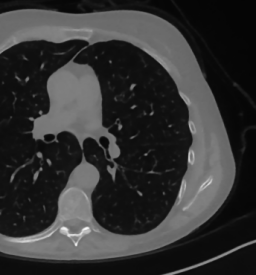

The considered images are pixel reconstructions of human abdomen, computed from full-dose acquisitions. In Figure 2 we depict one image with two zooms-in highlighting areas with different anatomical structures, such as pulmonary details, sections of ribs and low-contrast inter-costal muscles.

In all the experiments reported in 5.1, we have used the images from the data set as ground truth references.

Coherently, we simulate the tomographic projections of the ground truth images, according to a 2D fan-beam geometry, and we add to the sinograms white Gaussian noise with noise level.

To address sparse-view CT reconstructions, we considered two different protocols: the first one is a full angular acquisition with 1-degree spaced projections (we call it in the following); in the second one the scanning trajectory covers degrees and computed only projections (it is labelled as ).

The RIS step executes only iterations, hence we denote as the SGP output which is passed as input to the ING phase.